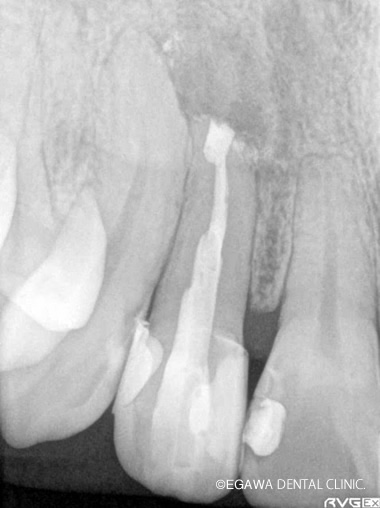

先端に病巣がありますが、歯根端切除とMTAセメントによる逆根管充填により病巣が治癒しています。

症例1

術前

術中

術後